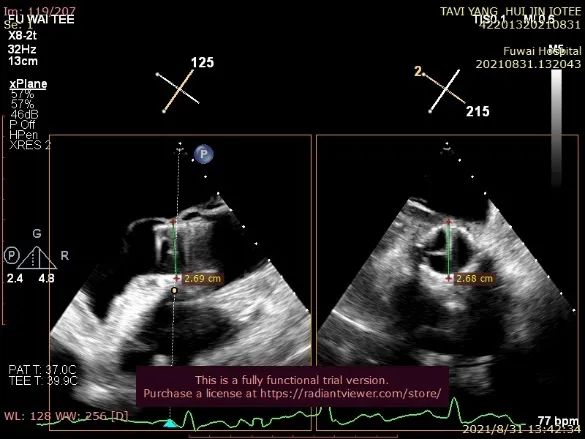

通过TEE确定三个定位件准确入窦后完全释放瓣膜(图4),再次用TEE观察人工瓣膜自膨后金属支架的形态(自膨胀后最大外径)、位置(瓣环下金属支架长度及占比)、有无明显瓣周漏。撤出输送器(图5),收紧心尖处荷包线并打结,检查无出血,逐层关胸,封皮,拔出股动脉鞘并在股动脉穿刺处压迫止血。手术过程顺利,患者生命体征平稳。

图4. TEE和放射线显示人工瓣膜自膨

术后即刻放射线显示人工瓣膜位置良好,随心跳运动,与周围组织无相对位移;TEE显示人工主动脉瓣金属支架位置良好,瓣环下支架长度约7mm,支架自膨后外径为26.8mm,接近瓣膜真实外径(图6),CDFI多角度观察,舒张期冠脉开口处血流通畅,左室流出道侧人工瓣和自体瓣环之间仅见微量反流信号(图7),收缩期人工瓣口流速良好(峰值流速:2.0m/s,峰值压差:17mmHg)(图8)。

图6. 人工瓣充分自膨后,TEE示瓣环下方金属支架长约7mm,约占瓣架总高度1/3